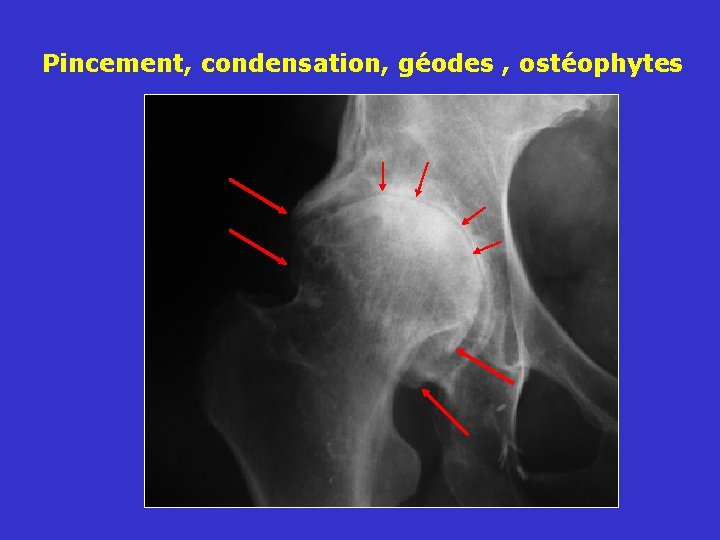

Les signes radiologiques de la coxarthrose Pincement, condensation, géodes , ostéophytes

Pincement, condensation, géodes , ostéophytes